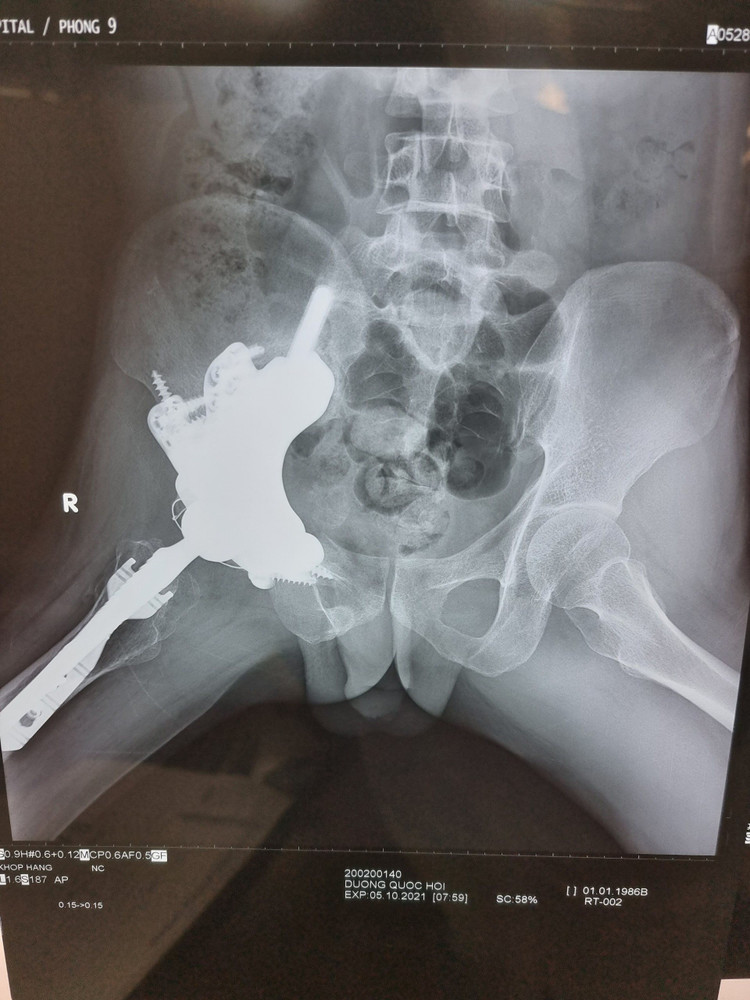

x-quang-sau-mo-3-thang.jpg

Xương của Hội phát triển tốt và dự kiến trong vài tháng tới, chàng trai trẻ có thể đi đứng bình thường.

Cuộc đại phẫu kéo dài hơn 10 giờ với sự tham gia của ê-kíp phẫu thuật đến từ nhiều chuyên khoa của Bệnh viện Chợ Rẫy TPHCM. Khối u khổng lồ đã được bóc tách thành công và các bác sĩ đã tạo hình khớp háng - xương chậu. Xương của Hội phát triển tốt và dự kiến trong vài tháng tới, chàng trai trẻ có thể đi đứng bình thường, quay lại với công việc cùng những ước mơ dang dở trước đây.